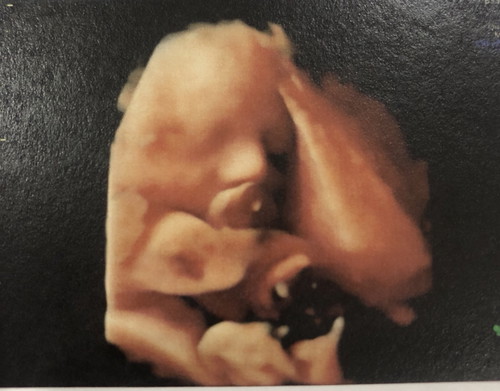

ขี้อาย

บ้านนี้ลูกขี้อายมากค่ะ หมอนัดทีไรเอามือปิดหน้าทุกทีเลย ล่าสุดเอาเท้าใส่หน้าด้วย แม่ได้เห็นแค่ตากับจมูกเอง บ้านไหนลูกขี้อายบ้างคะ 31w 3d แล้วค่ะ

แม่ลุ้นทุกรอบเลยค่ะ รอบที่แล้วก็เอาหน้าติดรก เอามือใส่หน้า รอบนี้หนักเลยค่ะ เอาเท้าใส่หน้า แม่เห็นแค่ตากับจมูก 🤣